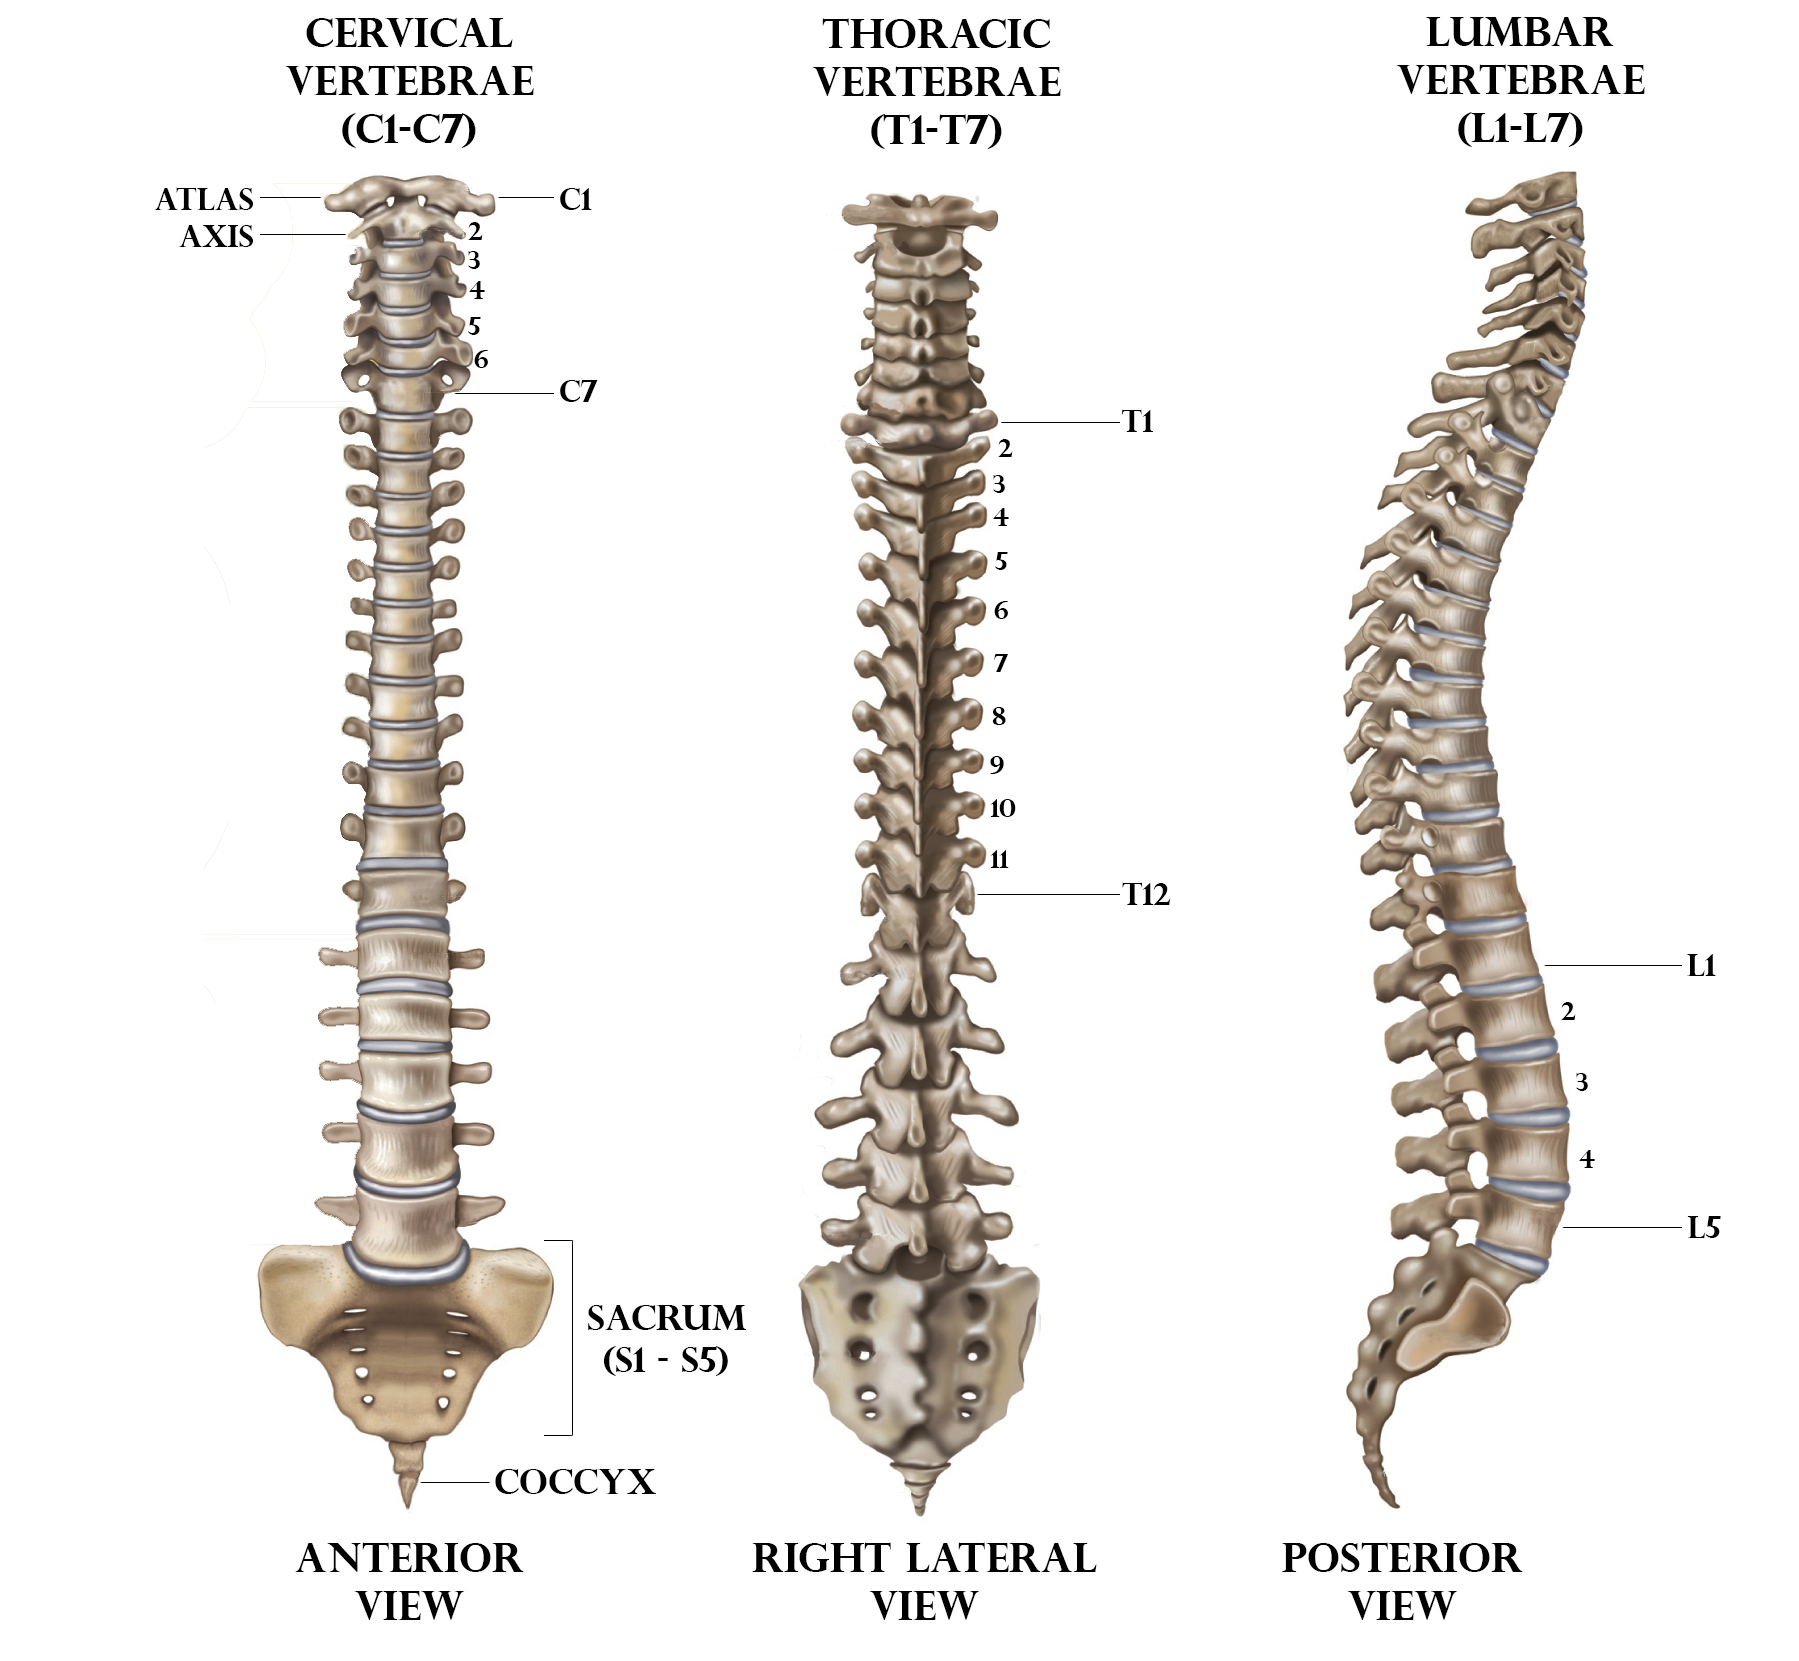

silikonsheet.blogg.se – Spine diagram

diagram of cervical and thoracic spine – Google Search | Spinal cord …

Bones-of-the-Spine-for-EMS – Handley Law

human spine anatomy diagram

Diagram Human Spine Name Description All Sections Vertebrae Vector …